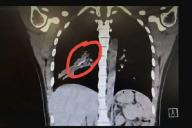

Светлана Протас Анастасия Заворотнюк актриса Instagram* медицина здоровье Шоу-бизнесДевушка 14 лет задыхалась от кашля, а врачи не могли поставить верный диагноз, пока на снимке не проявилось нечто интересное.

Анастасия Мороз общество и люди медицина здоровье Главные новости В миреМыши и крысы на участке – это головная боль для большинства дачников. На грядках начинают появляться мышиные норы, растения вянут и падают от повреждений корней.